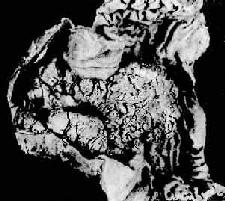

*因粘膜下层有癌组织生长 3.浸润型(infiltrating type)癌组织向胃壁内呈局限或弥漫浸润,与周围正常组织无明显边界。当弥漫浸润时致胃壁增厚、变硬,胃腔缩小,粘膜皱襞大部消失。典型的弥漫浸润型胃癌其胃状似皮革制成的囊袋,因而有革囊胃之称(linitis plastica)(图10-16)。

图10-16 弥漫浸润型胃癌 胃壁因癌组织的弥漫浸润而显著增厚 进展期胃癌的肉眼分型常用的还有Borrmann(B)分型。其中B1型为隆起型,B2型为限局溃疡型,B3型为浸润溃疡型,B4型为弥漫浸润型。 镜下,根据癌的组织结构,一般将进展期胃癌分为4种组织学类型: 1.腺癌(adenocarcinoma)最多见,癌细胞大多呈柱状,排列成腺腔(腺管状腺癌,glandular form)(图10-17),腺腔内出现许多乳头(乳头状腺癌,papillary form)。有的癌细胞呈立方形或圆形,由数个癌细胞形成小腺泡(腺泡状腺癌,acinar form)。此型癌组织分化较高,恶性度较低,转移较晚。